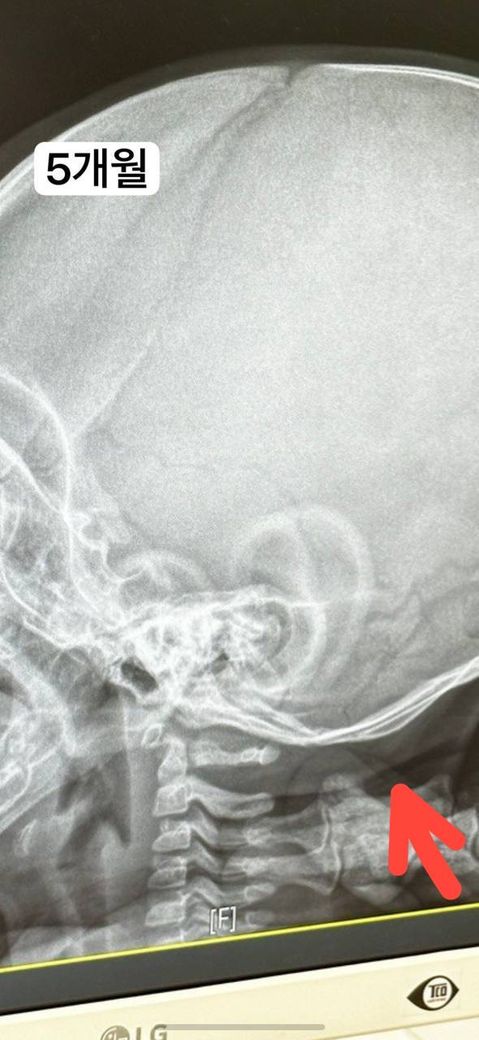

8개월 아기 낙상 엑스레이 사진 봐주세요

아기가 정수리 쪽으로 해서 침대에 떨어졌어요..

근데 뒷목쪽이 부어서

동네 정형외과 가보니까 두상 아랫쪽이 아기 뼈 열린 부위랑 이어져 보인다고 99퍼센트 골절은 아닌것 같지만 금이 가보이는 부위에 부은걸 봐서는 1% 확신 할 수 없다고 하셨어요..

5개월때 찍은 엑스레이 사진이랑 비교하면 차이가 나보여요.. 근데 정수리 쪽으로 부딪혔는데 두상 아랫쪽에 금이 갈 수 있나요..?

- 두상 아랫쪽 목 뒷부분 부어 오름

• 1번 째 사진